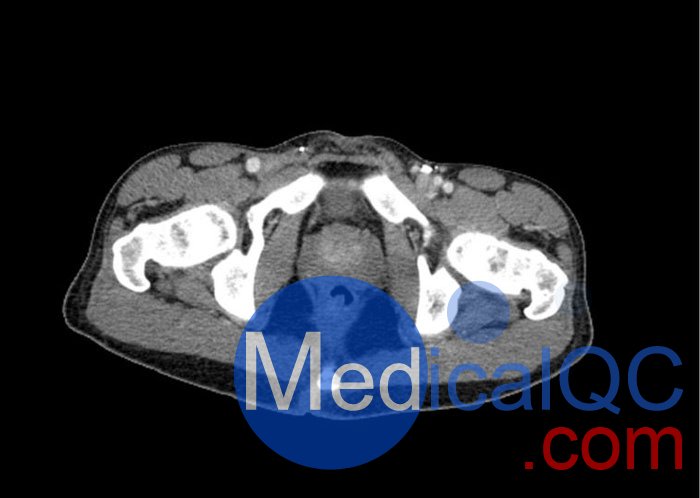

WEK57-01門靜脈期軀干模體,WEK57-01軀干模型模擬了門靜脈期的造影劑增強胸部、腹部和骨盆。它覆蓋了會陰的第二胸椎。

右側(cè)有髂淋巴結(jié)腫塊。

真實模擬脈管系統(tǒng)、骨骼和軟組織,包括肺、心臟、肝臟、膽囊、胰腺、脾臟、腎上腺、腎臟、胃、小腸、結(jié)腸、膀胱和前列腺。

右側(cè)髂外淋巴結(jié)腫塊。

WEK57-01門靜脈期軀干模體,WEK57-01軀干模型成像效果圖: